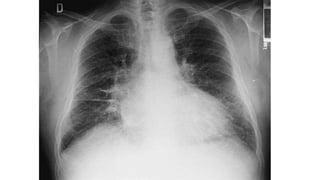

Radiografía de tórax

Líneas de Kerley

● Líneas A (largas finas y rectas) se aprecian

más a nivel del ápice del pulmón

● Líneas B (rectas y cortas) aproximadamente

de 2 cm de longitud, se encuentran

principalmente a nivel costodiafragmático.

cefalización del flujo

Hay una dilatación de los vasos sanguíneos de

los campos pulmonares superiores mayor a

3mm

Imagen en alas de mariposa

Infiltrado moteado difuso con bordes mal

definidos.

En caso de edema cardiogénico

Borramiento de los senos costodiafragmáticos

Cardiomegalia

Dilatación de vasos de campos

pulmonares superiores